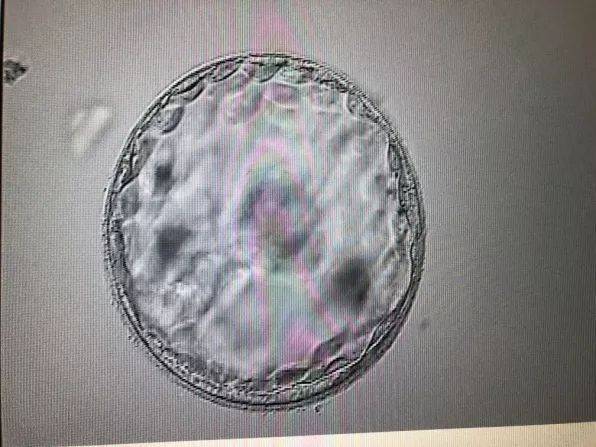

早期流产,是指妊娠在12周之前终止的现象。早期流产的原因有很多,包括染色体异常、内分泌失调、感染、免疫因素、环境因素等。在这些原因中,有的与休息有关,有的则与休息无关。